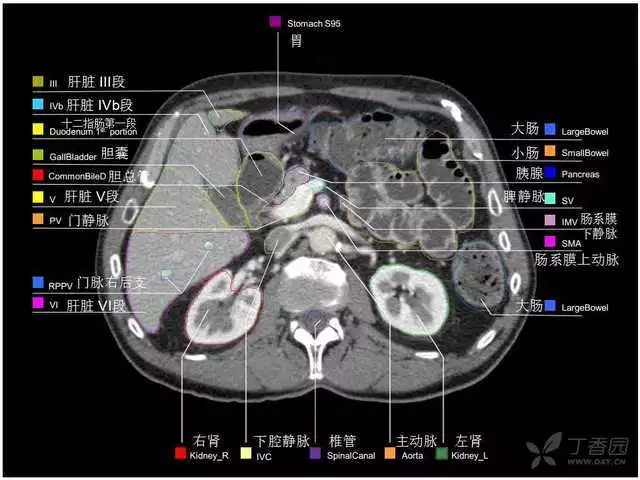

腹部肝脏高清CT断层的图谱

全腹部高清CT图谱,淋巴结彩色图谱,血管解剖图谱大汇总!

超声肝脏分叶及分段

肝脏分段和基本解剖学标志